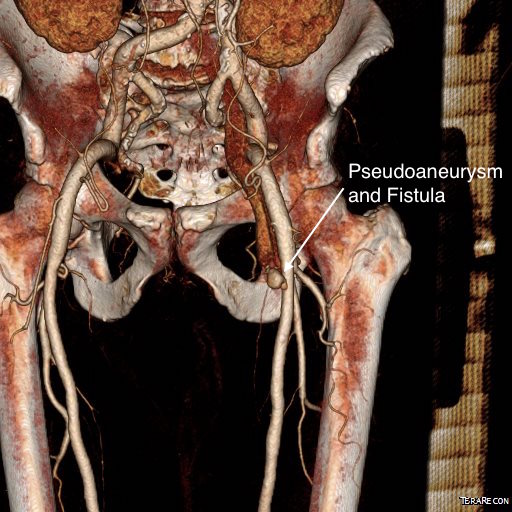

The bypasses were sent from the infrarenal aorta to the common hepatic artery and the SMA close to its origin, and the origins of the celiac axis and SMA were clipped. The bypasses were then done with a 10x8mm bifurcate Dacron graft originally for axillofemoral bypassing. It had spiral rings which I removed at the anastomosis and this resulted in a kink at the closer bypass. Usually, I loop this for iliomesenteric bypass but there was not enough distance from the infrarenal aorta. I have to add a little trick I modified from my pediatric surgery experience as a resident -a Heinecke-Mikulwicz graftoplasty:

This worked to relieve the kink as evidenced on the aortogram above. After closing the laparotomy, I placed a chest tube in the right chest. The patient had a course prolonged by a classic systemic inflammatory response syndrome, with fevers, chills, and leukocytosis. He bled for a while but stopped with correction of his coagulopathy. All blood cultures were negative, but a CT scan was performed out of concern for the endoleak, and the possibility of continued bleeding.

No endoleak was detected as the sac was fully thrombosed. There was a consolidation of the blood in the right chest, but it resolved with fibrinolytic therapy.